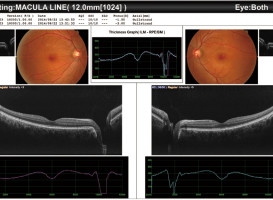

Fotografie této firmy